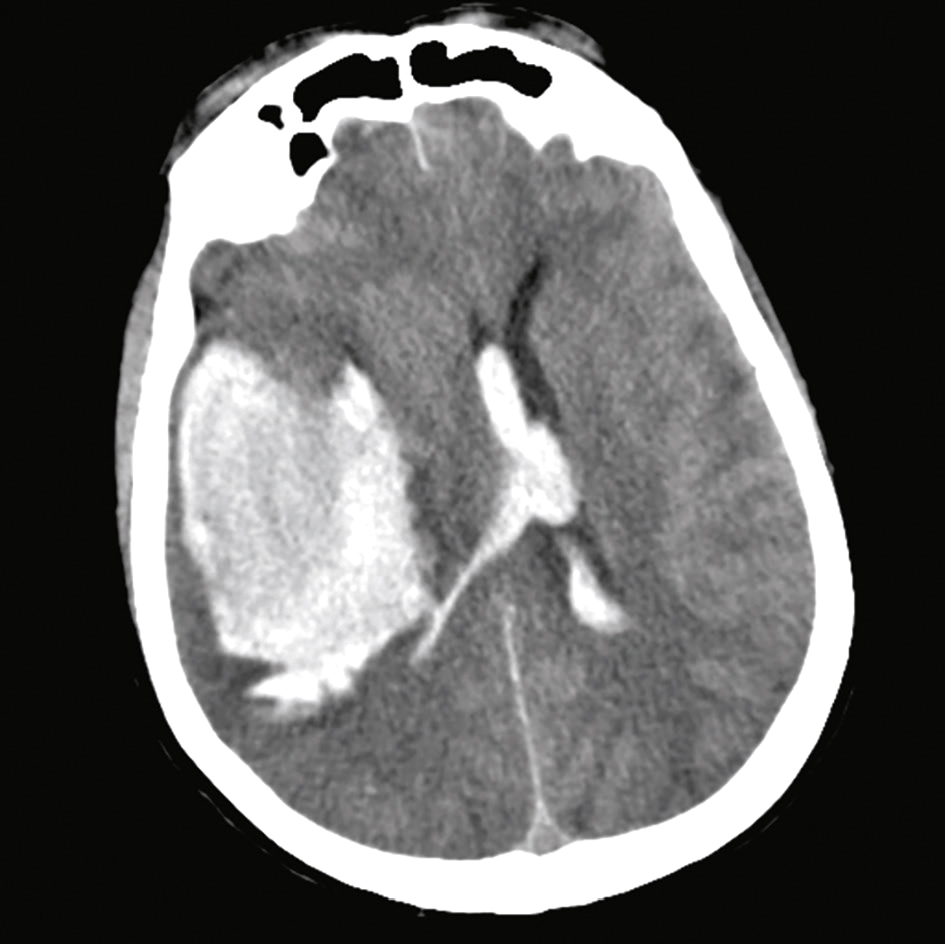

• scanner cérébral sans injection en urgence : il précise parfois d’emblée la nature lésionnelle d’un coma (hématome cérébral) et l’importance de l’œdème cérébral (fig. 27.1); il sera réalisé en l’absence de cause évidente, même en l’absence de signes de focalisation, surtout en cas de traumatisme crânien;

Fig. 27.1

Scanner cérébral : volumineuse hémorragie centro-hémispherique droite avec déviation ligne médiane traduisant un effet de masse et un engagement cérébral.